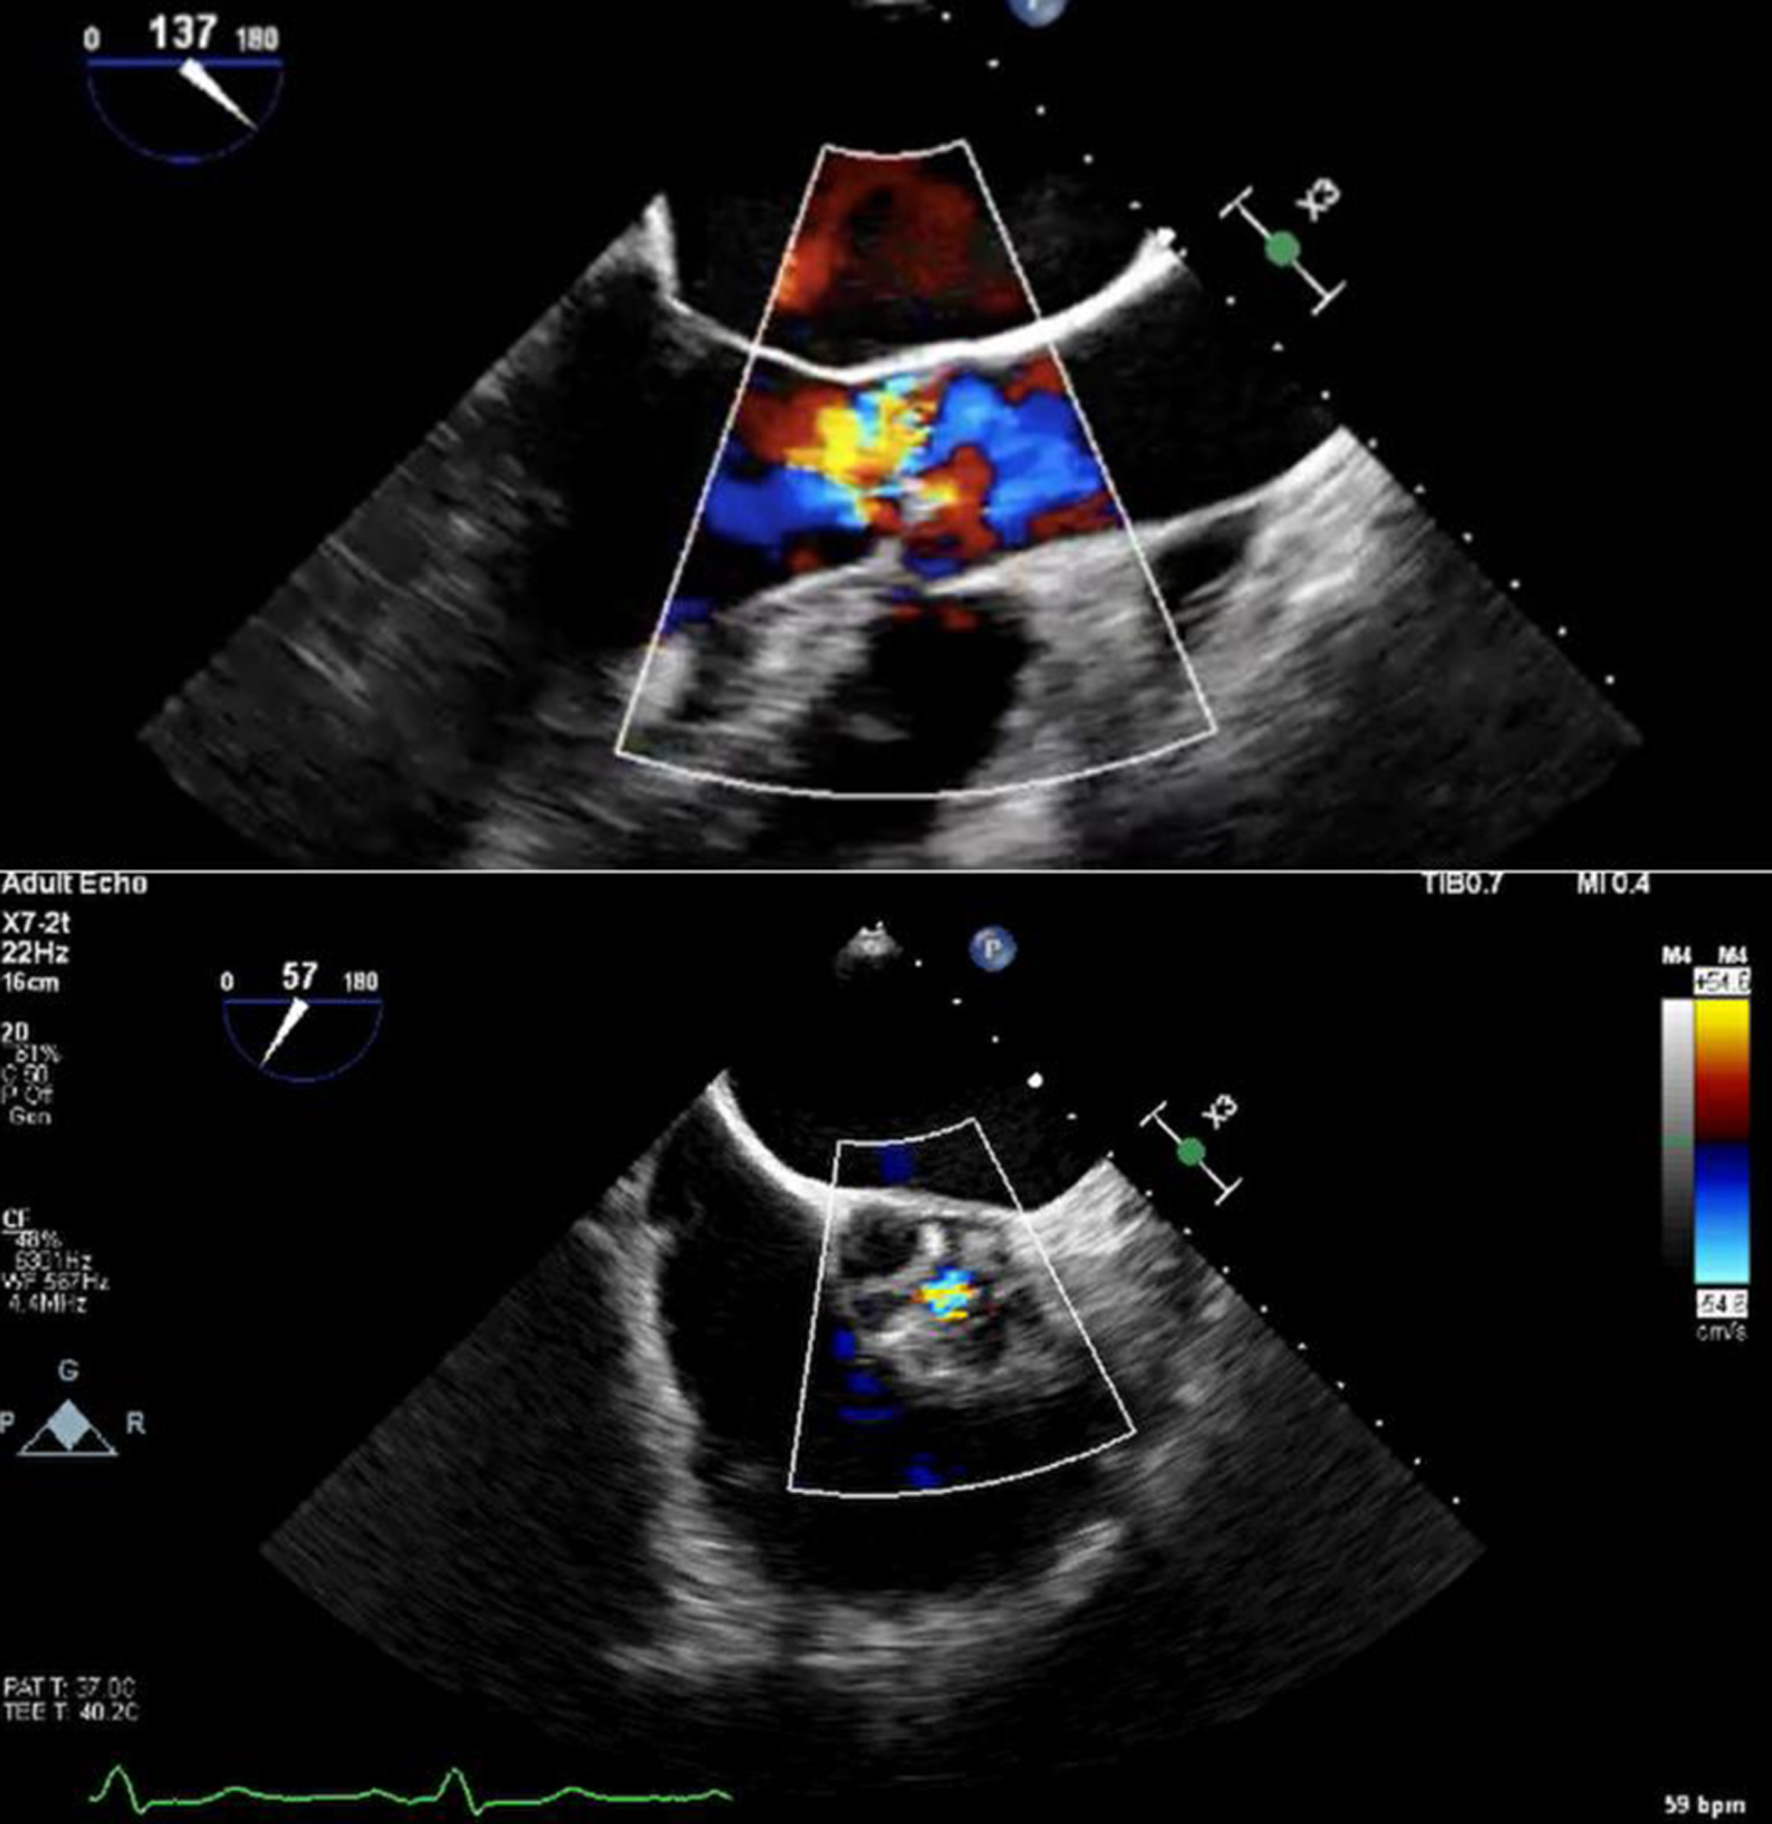

Initial bedside echocardiogram, done while intubated in ICU, showed LVEF of 30-35%, dilated LV at 6 cm, and a central jet of AR deemed moderate. Departmental TEE corroborated the impression of moderate AR. Quantitative assessment was, however, limited by eccentric AR jet (Fig. 1). Coronary angiogram showed no obstructive coronary artery disease. Two weeks later, CMRI showed a severely dilated LV with indexed end diastolic volume of 176 mL/m2 (Fig. 2). There was moderate eccentric LV hypertrophy, but preserved LVEF at 56% and stroke volume of 197 mL. Aortic valve images demonstrated a trileaflet aortic valve with partial fusion of the left and right coronary cusps, and severe AR due to failure of coaptation between these cusps (Fig. 3). Aortic regurgitant fraction was 45-50% by LV-RV stroke volume difference. Unfortunately, flow analysis was limited as the imaging plane was placed on the aortic valve rather than the sino-tubular junction, which would underestimate regurgitant fraction (Fig. 4). The AR was felt to be severe based on qualitative assessment, large, holodiastolic jet extending into LV, aortic diastolic flow-reversal, and regurgitant fraction > 45% plus LV dilatation. There was no systolic anterior motion or LVOT obstruction, and no late-gadolinium enhancement, suggesting no myocardial fibrosis, infiltration, or infarction. There was no fibrosis detected on T1 mapping. Discrepancy in LVEF between imaging modalities was explained by myocardial stunning post-arrest. AR severity was underestimated on echocardiography due to the eccentricity of the AR jet.

Figure 1. Color Doppler transoesophageal echocardiography showing eccentric aortic regurgitation jet, with short-axis view showing regurgitant jet through coaptation defect.